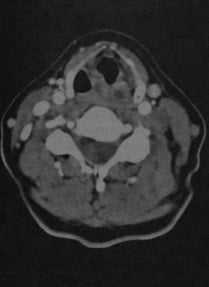

Тромбоз яремной вены. КТ с контрастированием: полная окклюзия левой внутренней яремной вены старым тромбом. Диаметр вены не изменен в сравнении с противоположной стороной. Просвет не заполнен контрастным веществом и имеет плотность немного ниже, чем окружающие мышцы. Заметно увеличение просвета наружной яремной вены, функционирующей как коллатеральный сосуд на стороне поражения.

КТ с контрастированием, горизонтальная проекция: свежий тромбоз правой внутренней яремной вены (а). Диаметр вены увеличен в сравнении с противоположной стороной, тромб имеет плотность значительно ниже, чем окружающие мышцы. На срезе, выполненном на несколько более высоком уровне (b), вокруг тромба выявляется тонкое кольцо в виде полумесяца.